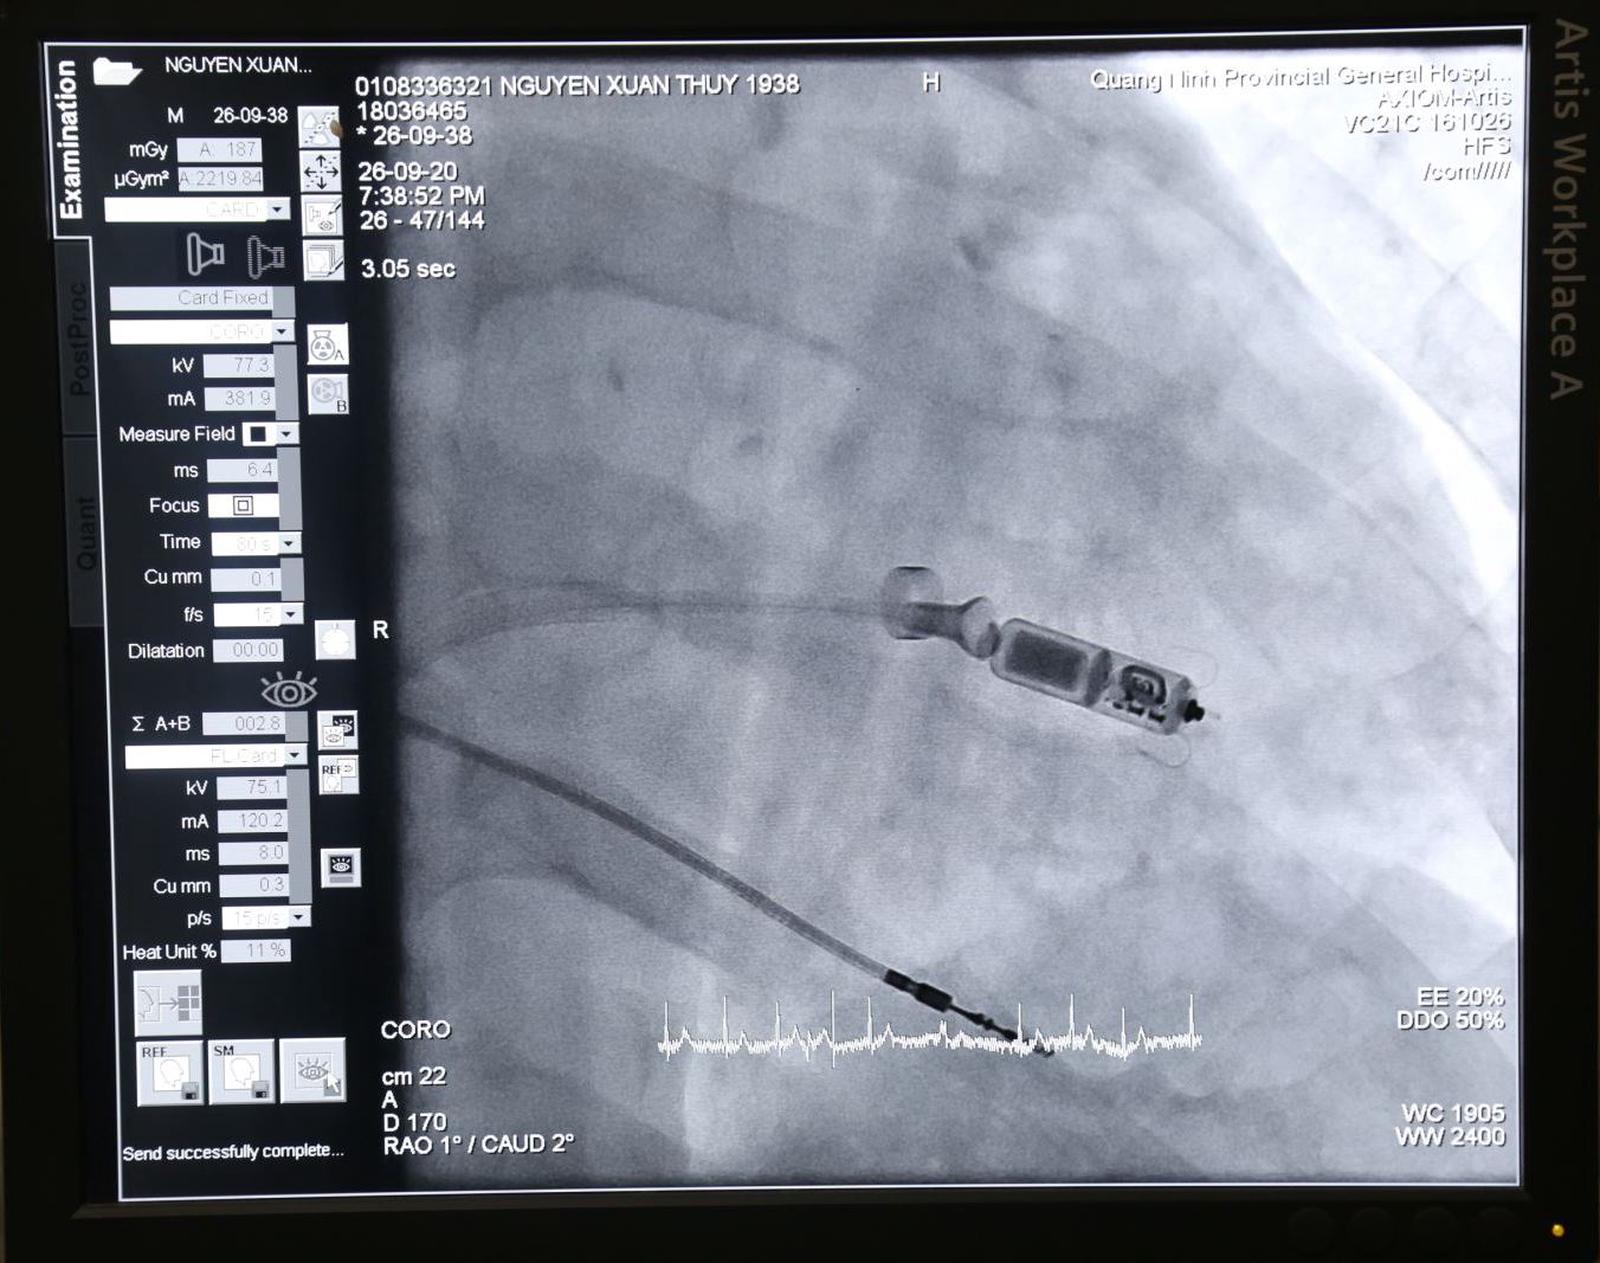

(Thanh tra) - Mới đây, Bệnh viện Đa khoa tỉnh Quảng Ninh phối hợp với Giáo sư, Tiến sĩ Võ Thành Nhân, Giám đốc Trung tâm tim mạch Bệnh viện Đa khoa Quốc tế Vinmec Central Park, Chủ tịch Hội can thiệp tim mạch TP HCM cùng ê-kíp của Bệnh viện thực hiện thành công ca đặt máy tạo nhịp không dây trực tiếp vào buồng tim cho bệnh nhân.

GS.TS Võ Thành Nhân cùng các bác sĩ Bệnh viện Đa khoa tỉnh tiến hành đặt máy tạo nhịp không dây cho bệnh nhân. Ảnh: HCQT

Đây là ca thứ 5 trên cả nước và là ca thứ 2 tại miền Bắc được áp dụng thành công kỹ thuật mới này.

Bệnh nhân Nguyễn Xuân Th. (82 tuổi, địa chỉ tại phường Cẩm Sơn, TP. Cẩm Phả) nhập viện trong tình trạng suy tim, nhiễm trùng ổ máy tạo nhịp, nhiễm khuẩn huyết/rung nhĩ đáp ứng thất chậm.

Được biết, trước đó bệnh nhân Th. đã đặt máy tạo nhịp vĩnh viễn thông thường (có dây). Bệnh nhân đã cải thiện triệu chứng nhiều, không còn những cơn ngất, sức khỏe hồi phục dần dần. Tuy nhiên, trước 1 tuần nhập viện vùng ngực trái vị trí cấy máy tạo nhịp ở dưới da sưng nề đỏ, đau rát nhiều và chảy mủ, chảy dịch làm bệnh nhân rất khó chịu và mệt mỏi.

Sau khi hội chẩn đánh giá, các bác sĩ đánh giá bệnh nhân cần phải được can thiệp lấy máy tạo nhịp ra và tiến hành khử trùng, vệ sinh sạch sẽ ổ máy. Nhưng rút bỏ máy tạo nhịp ra, bệnh nhân lại xuất hiện nhịp tim chậm sẽ nguy hiểm đến tính mạng của bệnh nhân. Mặt khác, sau khi loại bỏ máy tạo nhịp cũ sẽ phải cấy máy tạo nhịp mới đưa vào buồng tim ở vị trí khác so với vị trí ban đầu, tiên lượng nguy cơ nhiễm trùng máy tạo nhịp thứ hai rất cao.

Bệnh viện Đa khoa tỉnh Quảng Ninh cho biết, trước thực tế đó, bệnh viện đã chọn giải pháp là mời trực tiếp Giáo sư, Tiến sĩ Võ Thành Nhân, Giám đốc Trung tâm tim mạch Bệnh viện Đa khoa Quốc tế Vinmec Central Park, Chủ tịch Hội can thiệp tim mạch TP HCM cùng ê-kíp của Bệnh viện đến triển khai kỹ thuật mới đặt máy tạo nhịp không dây.

Sau khi can thiệp thành công, bệnh nhân đã tỉnh táo, tim hoạt động gần như bình thường.

Ưu điểm của máy tạo nhịp không dây là sẽ tránh được nguy cơ nhiễm trùng tái phát ổ máy tạo nhịp dưới da. Máy có kích thước rất nhỏ, chỉ như viên thuốc con nhộng và trọng lượng chỉ có 2g nhẹ hơn tới 93% so với máy tạo nhịp tim thông thường (28g). Loại máy này cho phép tạo nhịp tim cho bệnh nhân trong thời gian có thể đến 12 năm.